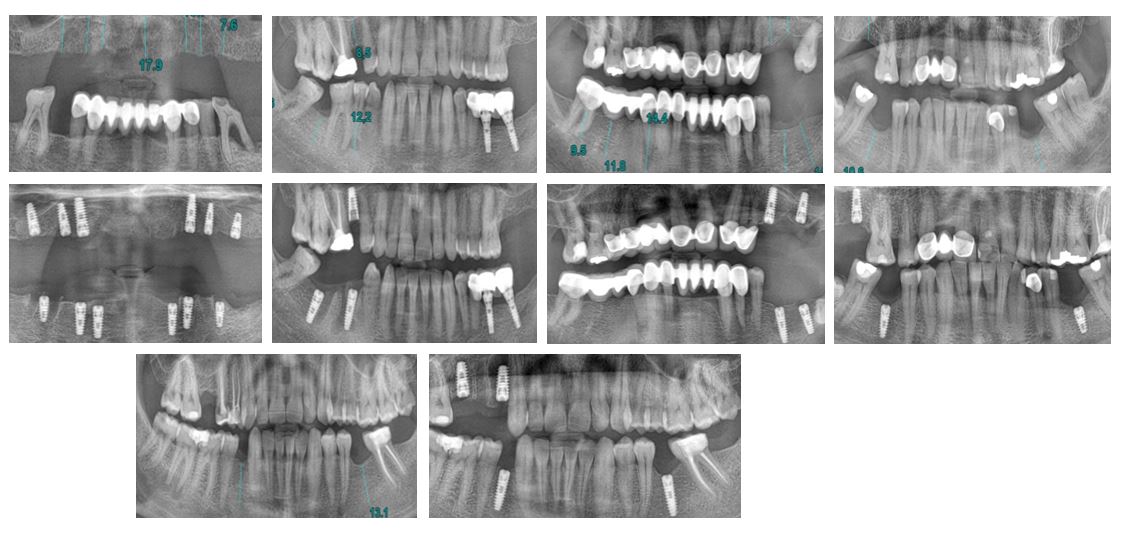

Bölge 2430 Diş Sağlığı Bölge Ana Komitesi’nden sağlanan implant desteği ve Bölge 2430 Şehit ve Gazilerimiz Bölge Ana Komitesi’nin yönlendirmeleri ile 4 Şehit yakını ve 1 Gazimizin ücretsiz 26 implantlık tedavisi yapılmıştır. Proje kapsamında Dönem Başkanı Necmettin Yeta ve Eşi Naz’ın kliniği DentPro’da gerçekleşen tedaviler muayene, ölçüm, işlem, kontrol adımları ile hasta başına 4 klinik ziyareti olmak üzere toplamda 1 ay sürmüştür. Proje kapsamında şehit yakını ve gazilerimizin kontrolleri proje bitiminde de devam etmiş, Mart sonuna kadar